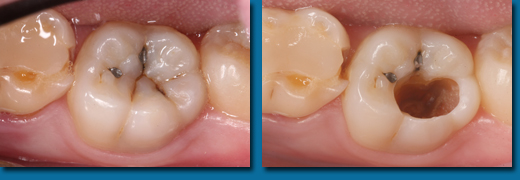

専門的にはう蝕診断といいますが一般の方が思うほど簡単なものではなく、集団検診でも歯科医院でも見逃されることが多くあります。写真の歯はいままで虫歯ではないと言われていましたが冷たいものがしみたり痛みがあったそうです。当院で調べてみると大きな虫歯が中で拡がっていることがわかりました。虫歯の入り口は小さくても中で大きく拡がっていることが多くあります。色々な診査器材を使用して虫歯も虫歯になりやすい歯も見逃しません。